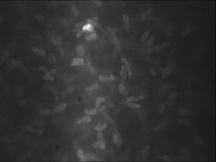

KERATOCYTES

Occupying 3% to 5% of the total stromal volume, keratocytes are interspersed throughout the corneal stroma and form a communicating network through their branching stellate processes. With confocal microscopy, keratocytes appear to be less densely dispersed than in Bowman's layer (Fig. 15). In the deep stroma, keratocytes appear spindle-shaped and more numerous than in the midstroma (Fig. 16).

Fig. 15. Confocal microscopic transverse image of the human mid-stroma in vivo. The keratocyte nuclei appear less dense than in Bowman's layer and less refractile. Note the highly refractile nucleus in the upper part of the image. This may be an activated keratocyte (500×). (Courtesy of Nidek Technologies.)

Fig. 16. Confocal microscopic transverse image of the human deep-stroma in vivo. Many of the keratocyte nuclei at this level are spindle-shaped and appear dense in numbers compared to the central cornea (500×). (Courtesy of Nidek Technologies.)